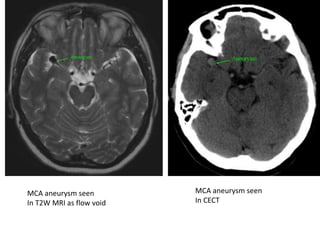

Aneurysms

Anterior communicating Artery aneurysm

Bilobed aneurysm at Rt MCA bifurcation

3D TOF MRA demonstrates a 6 mm aneurysm arising

from the basilar artery tip and projecting anteriorly

MCA aneurysm seen

In T2W MRI as flow void

In CECT